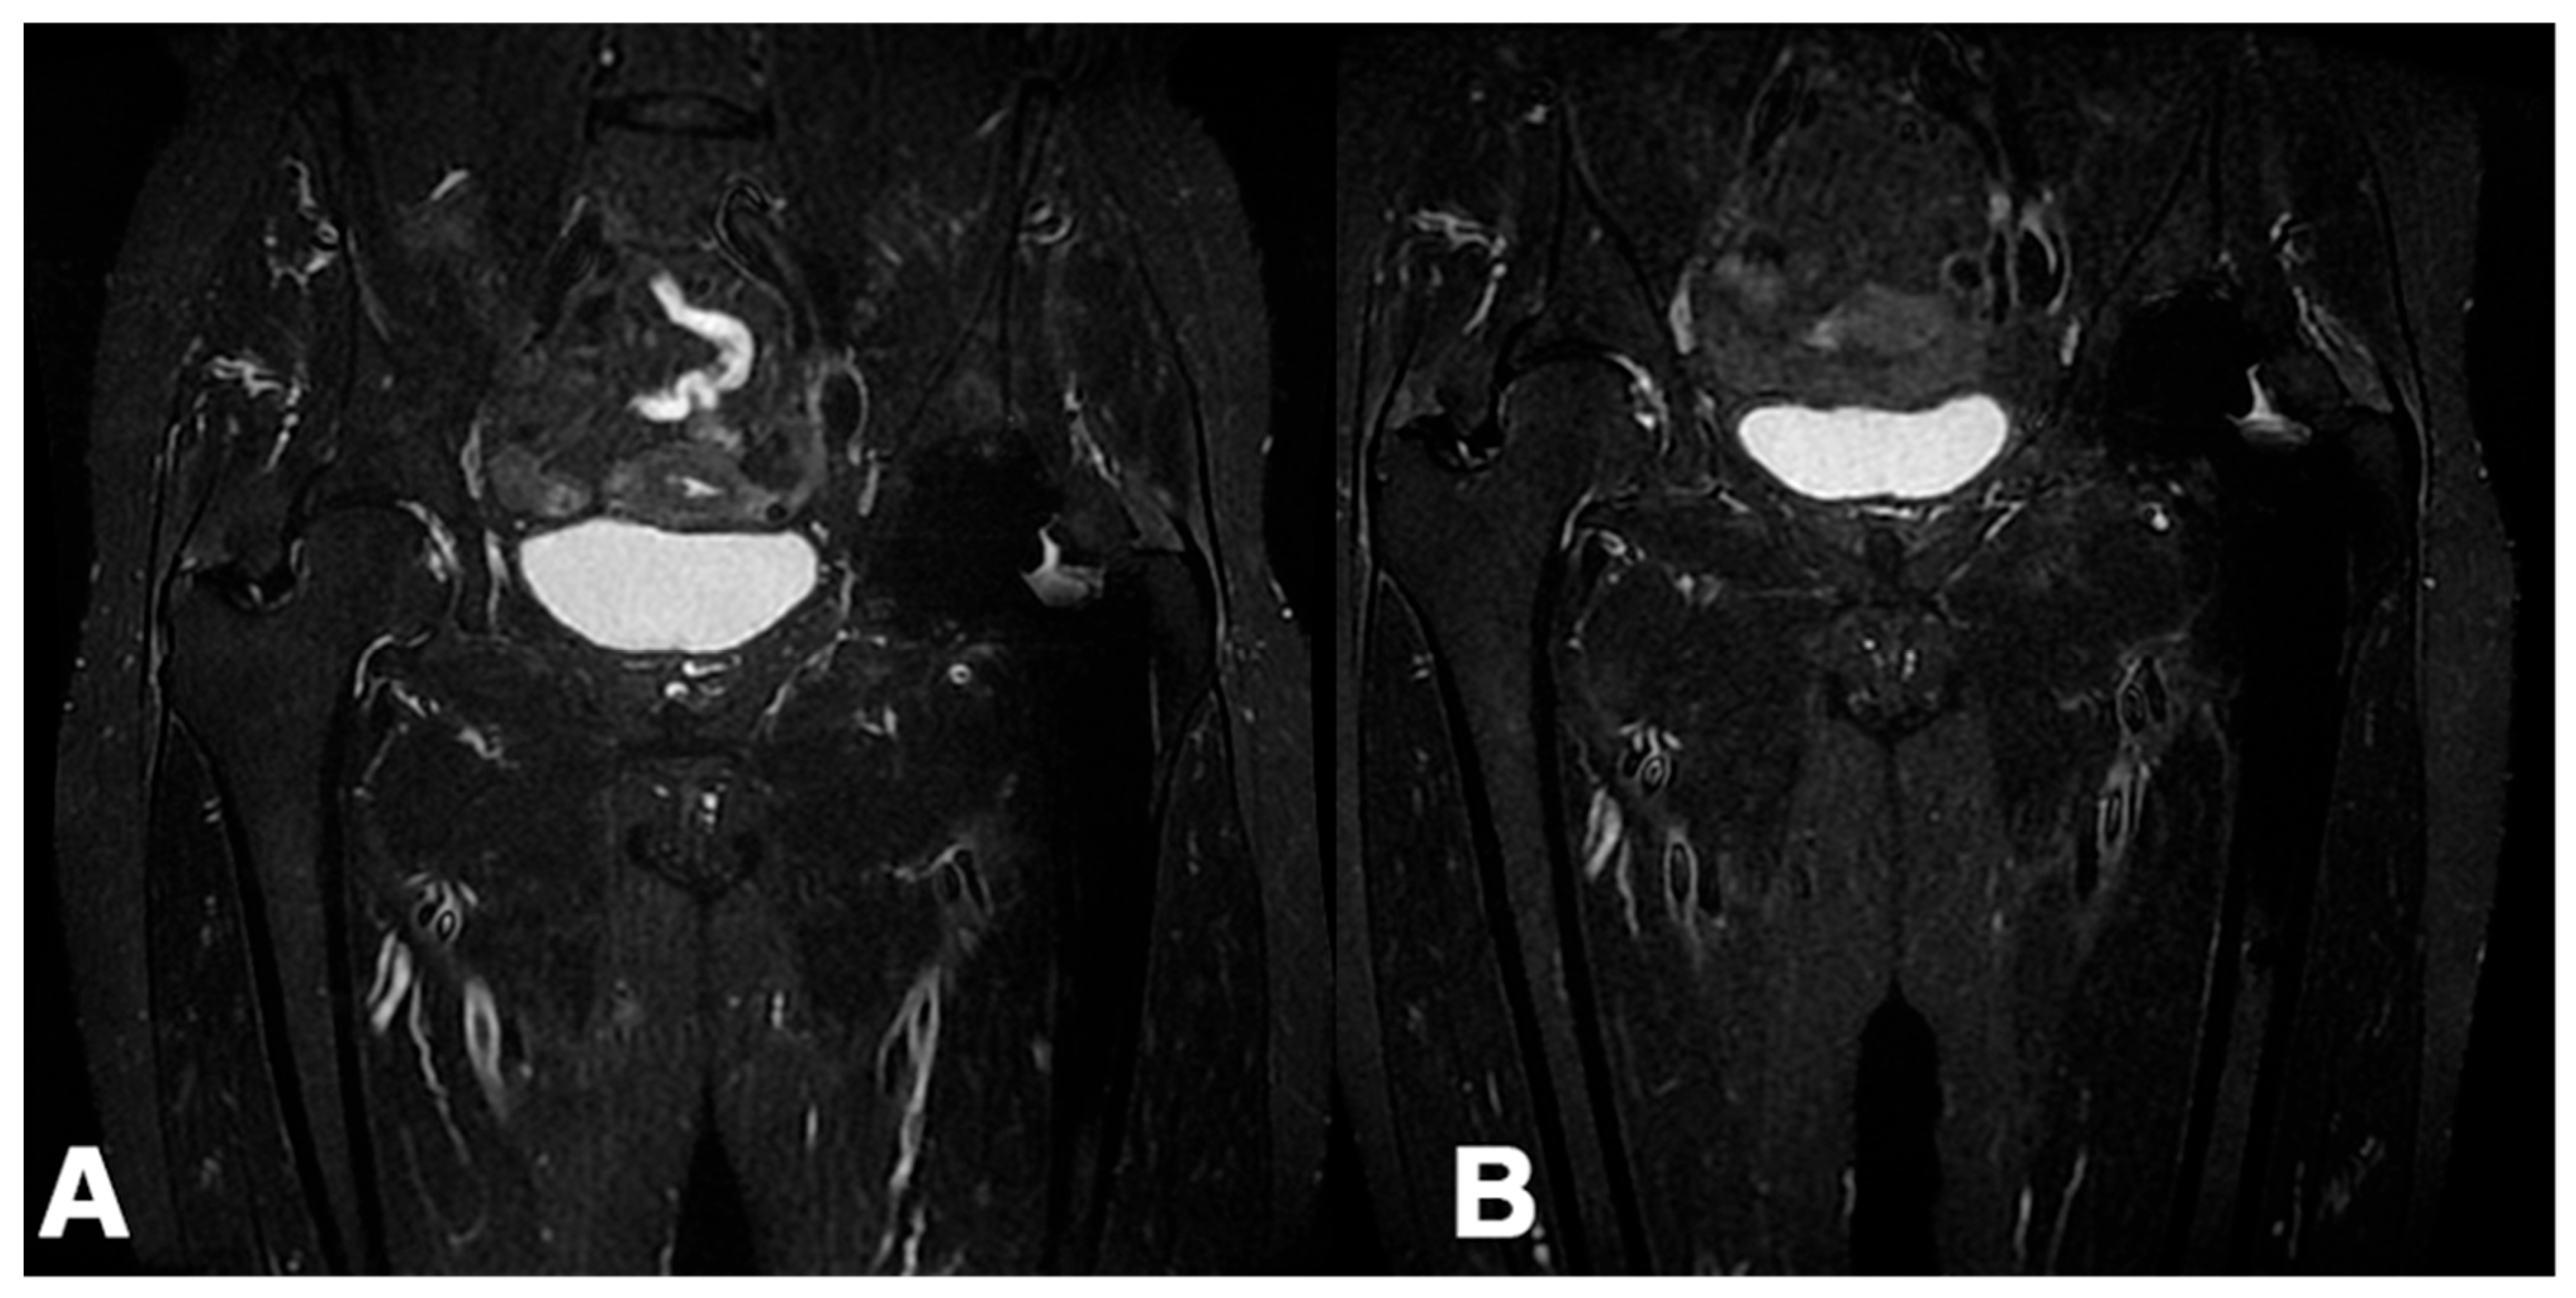

3.2.6. MRI

MRI images of the peritrochanteric area after six months (T24/FU) were available for 40 patients. In 25 patients (62.5%), a reduction in peri-tendinous edema was visible between the MRI performed before treatment and the one obtained at T24s/FU (Figure 6), while in 15 (37.5%), no changes were found. The paired samples t-test was statistically significant at p < 0.001. Interestingly, a linear correlation between pain reduction and improved MRI images was not always found, and vice versa.

MD-Tissue treatment also showed favorable MRI imaging and reduced peri-tendinous edema in more than 60% of treated patients. However, imaging improvements did not always correlate with clinical ones. The inadequacy of the follow-up could partly explain this difference. A visible biological response at MRI imaging, as an end-up result of cellular metabolic changes, may take longer to be observable. On the other hand, some patients without significant pain improvement showed a subjective reduction in peri-tendinous edema. This finding could be explained by the intrinsic difficulties in evaluating the peri-trochanteric space, the subjectivity of the methodology, and a need for complete knowledge about pain generators of the area.

Figure 6. A) Pre-treatment MRI coronal STIR sequence of a right hip affected by GTPS with the presence of a fluid signal in the insertional area of the gluteus medius tendon; B) MRI coronal STIR sequence of the same hip at T24s/FU with the presence of a homogeneous signal of the tendon.